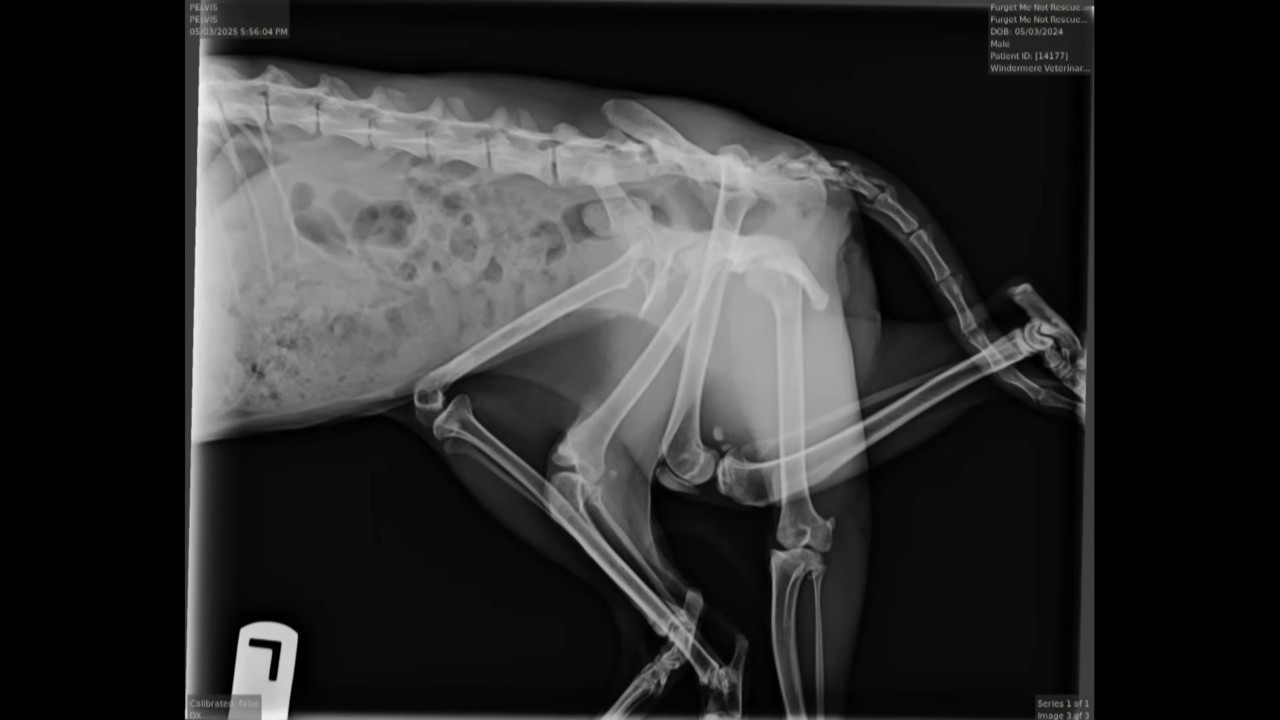

Veterinari iz "Windermere Veterinary Hospital" su uradili rendgenske snimke i procenili da bi operacija značajno poboljšala kvalitet njenog života.

Foto: Jutjub printskrin/CBC News: The National